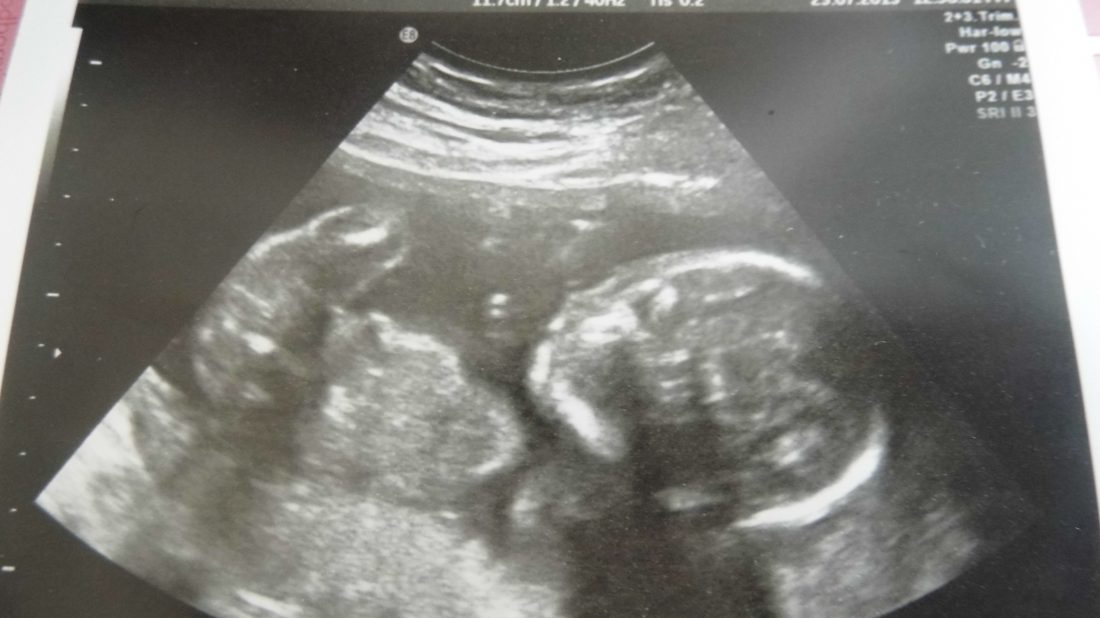

Nějak jsem v úterý večer dostala křeče od ledvin, které se tvářily jako kontrakce a tak jsme pro jistotu vyrazili s manželem do Podolí a tam si nás nechali. Ano, čekáme holčičku, a jak už jsem již psala bude to Klárka.